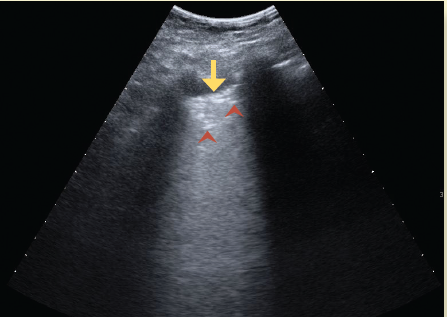

El ultrasonido es un método seguro, transportable a la cama del paciente, libre de radiación ionizante y de bajo costo, por lo que es útil en el diagnóstico y monitoreo de pacientes con infección por SARS-CoV-218. El hallazgo principal en ultrasonido es la enfermedad intersticial aguda, que produce artefactos hiperecoicos verticales que se apartan de la línea pleural, llamadas líneas B. El pulmón que pierde su contenido aéreo progresa de presentar un patrón pulmonar normal (con líneas A, las cuales se caracterizan por ser horizontales, cortas e hiperecoicas) a observar líneas B no coalescentes, después líneas B coalescentes hasta llegar a la consolidación19-21 (figuras 5a, 5b, 5c, 5d).

Figura 5d Ultrasonido en escala de grises del tórax, donde se observa la línea pleural (flecha amarilla) y áreas hiperecoicas irregulares (puntas de flecha) que corresponden al broncograma aéreo en un área pulmonar de consolidación